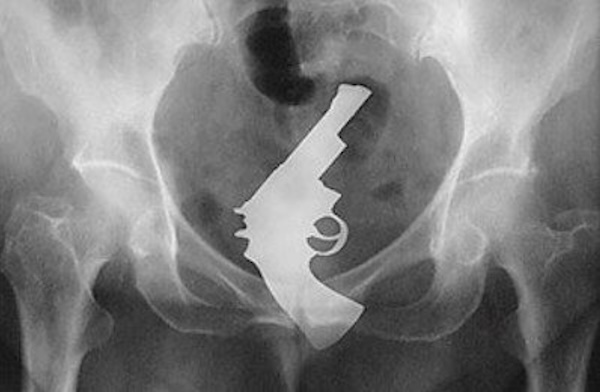

humanity 3802 Liked! 18 Disliked 0 Strange and Bizarre X-Rays that fracture logic itself (31 Photos) by: Ben In: Humanity, Interesting, Science, Shocking, Weird Oct 24, 2024 3802 Liked! 18 Disliked 0 1 We’ve all heard the idiom “It’s what’s on the inside that counts,” and we’re assuming whoever came up with that never got to look at an x-ray of a gun stuffed in someone’s ass. Still a nice phrase though, I guess. Like this post? 3802 Liked! 18 Disliked 0